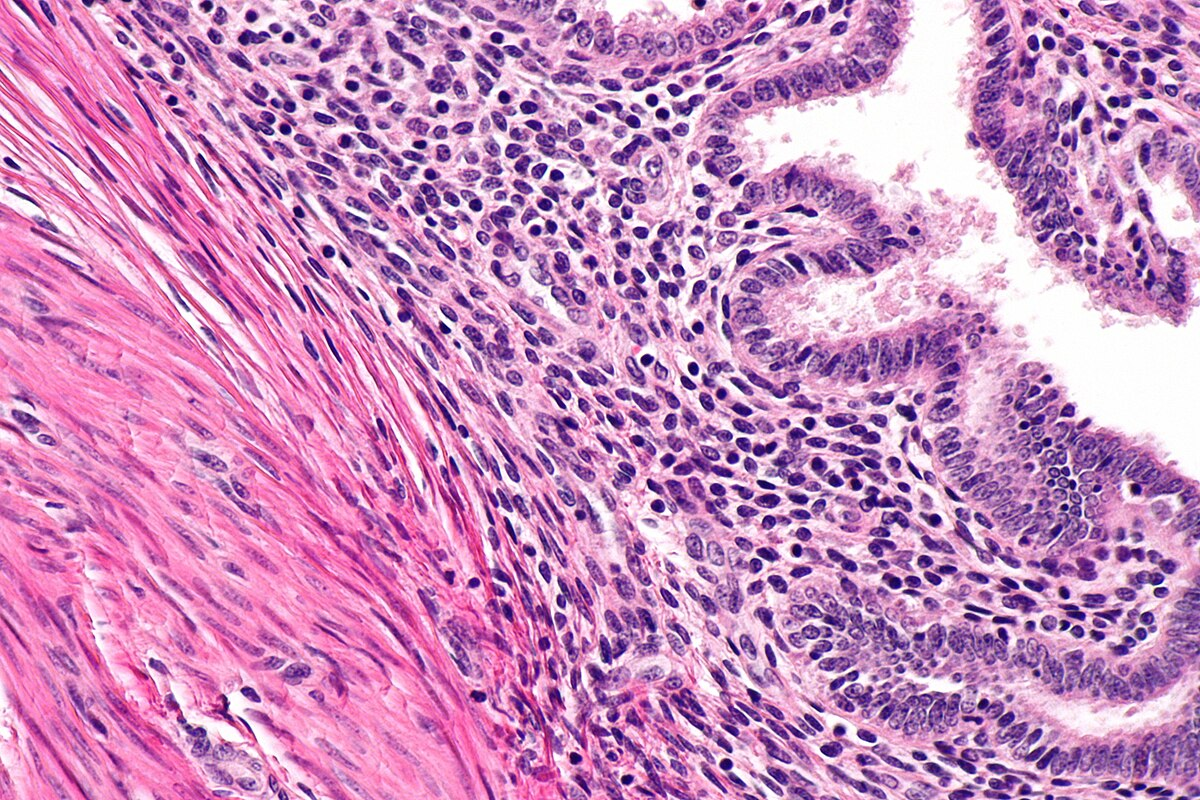

• Biopsy: Rarely, a small sample of tissue (from a muscle, skin rash, or artery) may be removed for examination under a microscope, especially when diagnosing vasculitis.